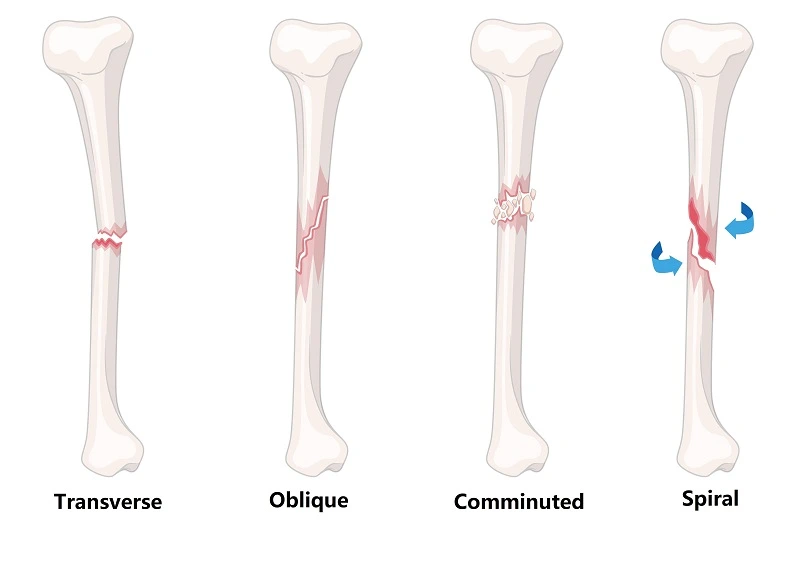

What Are Fractures?

A fracture is a partial or complete break in a bone caused by trauma, falls, overuse, or certain medical conditions that weaken bones. Proper recovery requires not just healing of the bone, but also restoration of muscle strength, flexibility, and joint function.